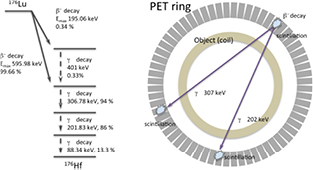

The Lutetium isotope 176Lu has a half-life of  years (e.g. Kossert et al (2013)) and decays predominantly via

years (e.g. Kossert et al (2013)) and decays predominantly via  decay with a maximum

decay with a maximum  -energy of 596 keV followed by three prompt γ-photons with energies of 306.78 kev, 201.83 keV, and 88.34 keV and abundances of 94%, 86%, and 13.3%, respectively. The decay scheme is shown in figure 1, left. The

-energy of 596 keV followed by three prompt γ-photons with energies of 306.78 kev, 201.83 keV, and 88.34 keV and abundances of 94%, 86%, and 13.3%, respectively. The decay scheme is shown in figure 1, left. The  -particle will be stopped in the same scintillation crystal where the decay takes place, since the range of β particles in solids is very short. However, the prompt γ-photons can escape from the scintillation crystal and can evoke additional scintillation events in other detector modules of the scanner (figure 1, right). Since the energy, the abundance, and the escape probability of the 88 keV prompt γ-photon is very low, three main types of coincidences, with corresponding lines of responses (LOR), will be observable if the energy acceptance window is sufficiently large: coincidence between

-particle will be stopped in the same scintillation crystal where the decay takes place, since the range of β particles in solids is very short. However, the prompt γ-photons can escape from the scintillation crystal and can evoke additional scintillation events in other detector modules of the scanner (figure 1, right). Since the energy, the abundance, and the escape probability of the 88 keV prompt γ-photon is very low, three main types of coincidences, with corresponding lines of responses (LOR), will be observable if the energy acceptance window is sufficiently large: coincidence between  and 307 keV γ, coincidence between

and 307 keV γ, coincidence between  and 202 keV γ, and triple coincidence between

and 202 keV γ, and triple coincidence between  , 307 keV γ, and 202 keV γ. Along their paths, the γ-photons will be attenuated according to the Beer-Lambert law

, 307 keV γ, and 202 keV γ. Along their paths, the γ-photons will be attenuated according to the Beer-Lambert law

Figure 1. Left: decay scheme of 176Lu. Right: most probable coincidences from 176Lu in the MR-BrainPET scanner.